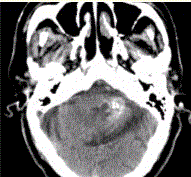

问题 男性,80岁,左耳听力下降伴头晕半年。头CT显示如下图。 诊断应为(提示进一步MR检查,病变显示如下图。)

选项 A.钙化灶 B.急性出血 C.动静脉畸形 D.海绵状血管瘤 E.胶质瘤 F.发育性静脉畸形 G.脑囊虫

答案 D